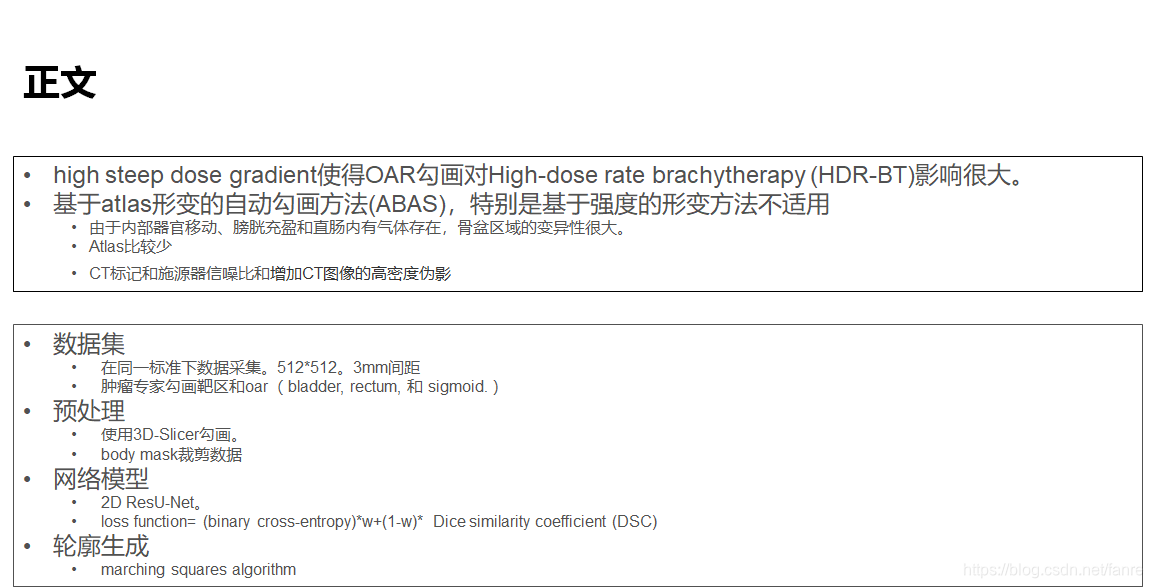

基于深度学习的宫颈癌高剂量率后装放疗危及器官自动勾画

基于深度学习的宫颈癌高剂量率后装放疗危及器官自动勾画